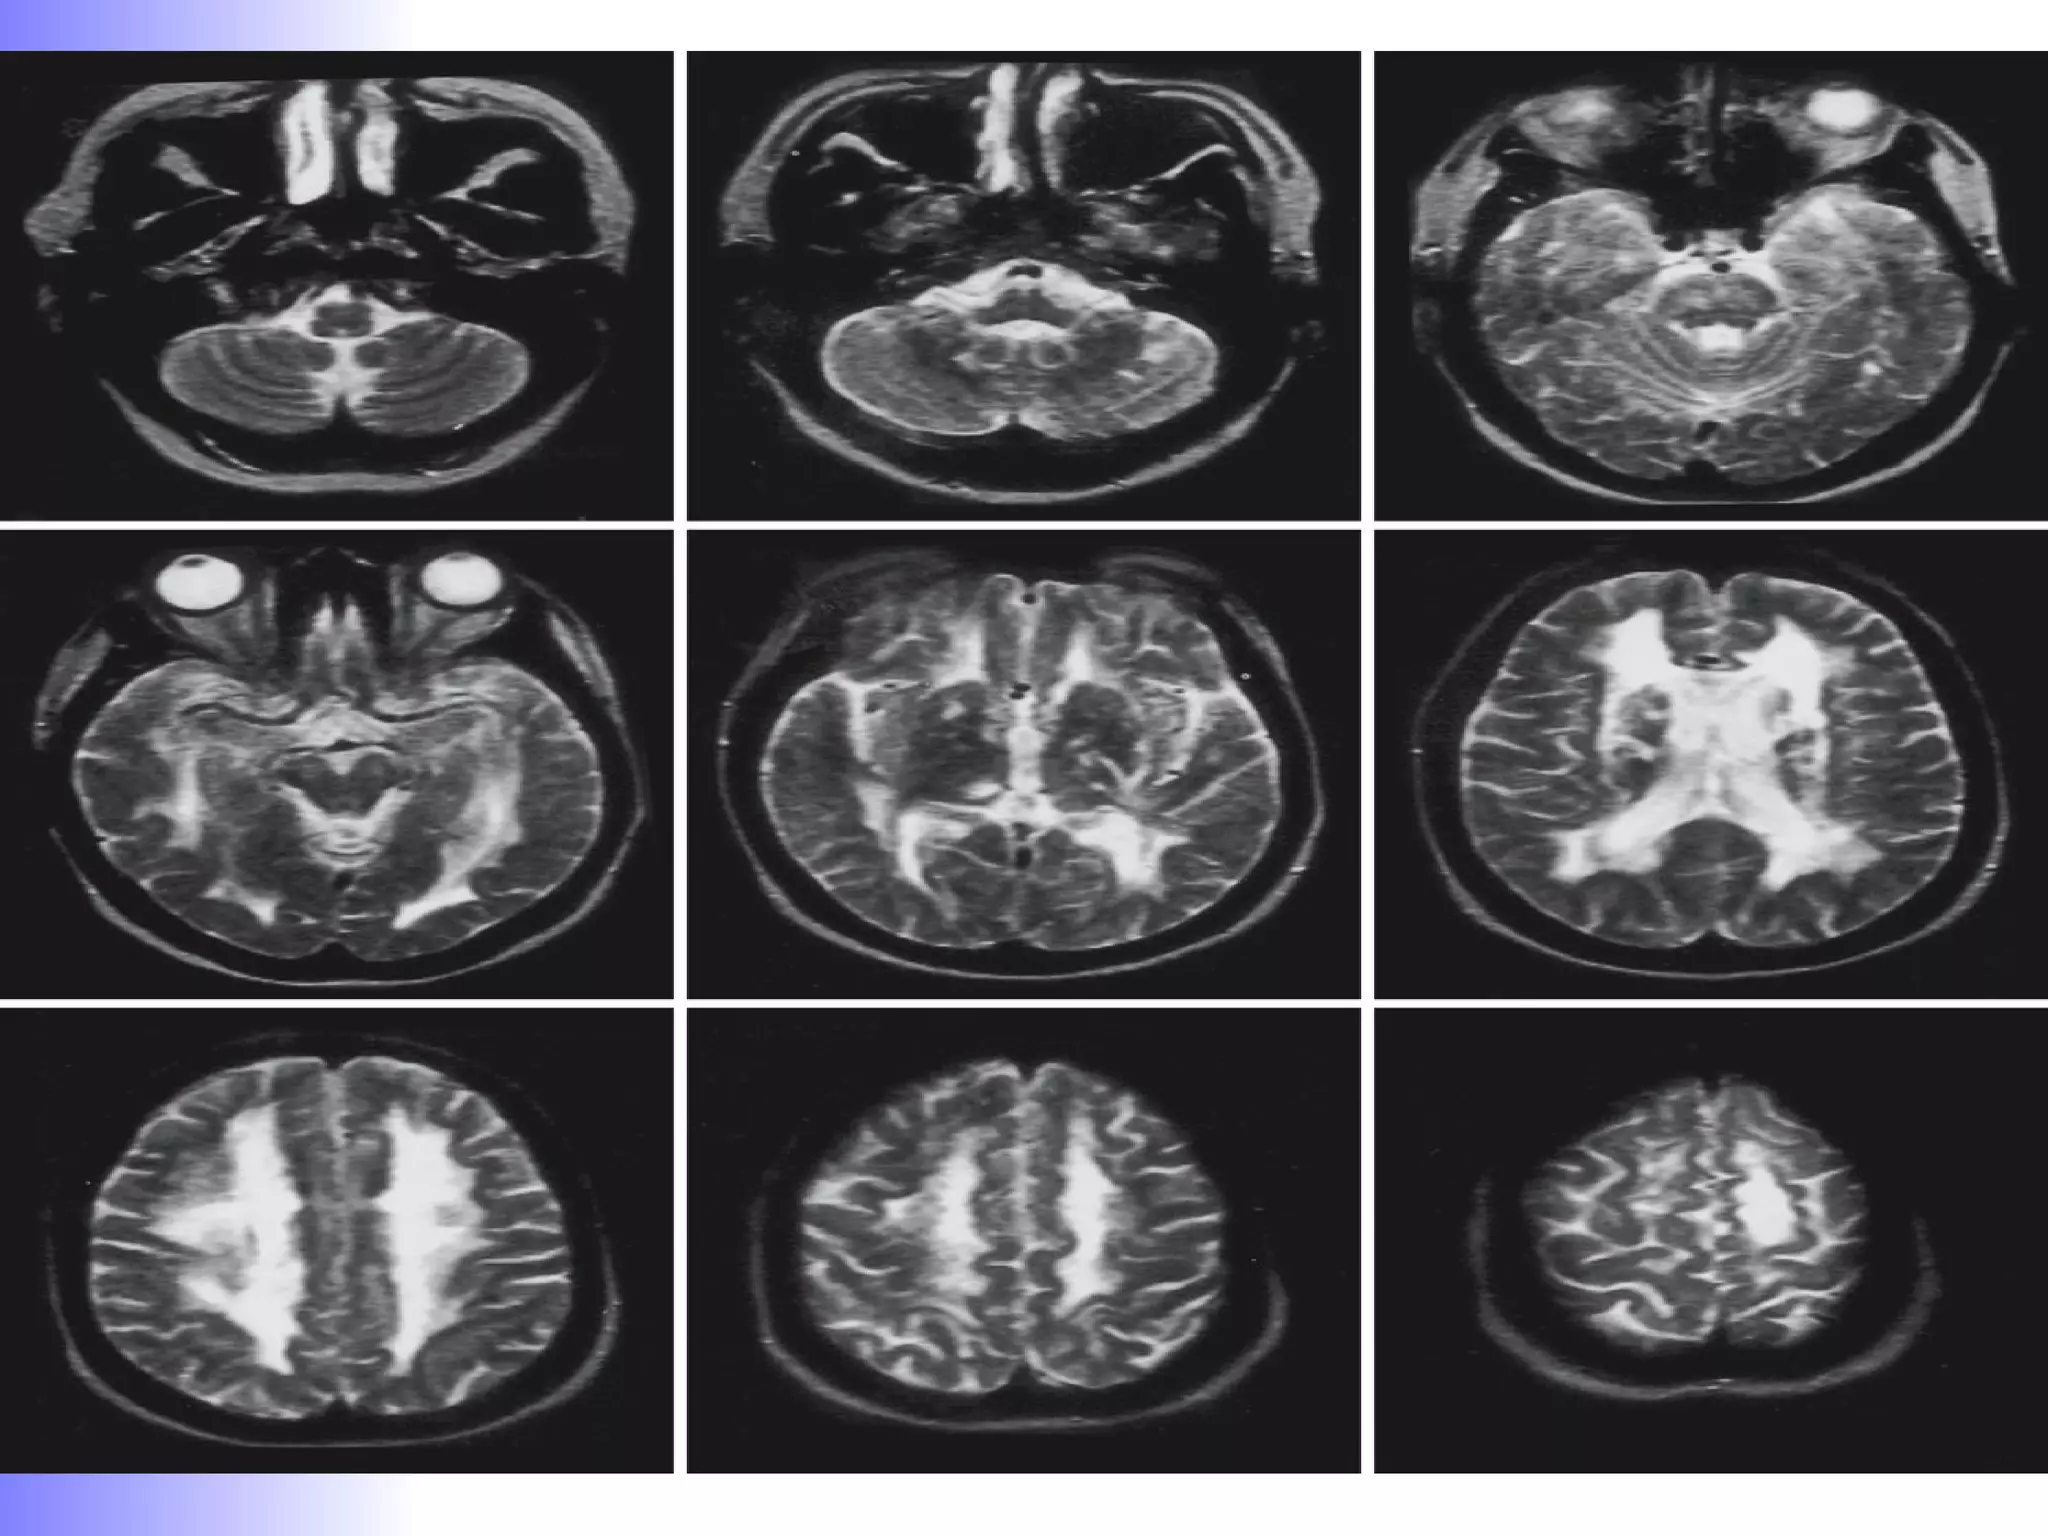

TRIAD :  Dementia + gait disturbance + Urinary incontinence. AGE :  usually after 60 yrs. Theories:  Impaired extraventricluar CSF absorption due to prior subarachnoid hemorrhage / meningitis.  Decrease white matter tensile strength due to deep white matter infarction / ischemic changes . Three primary MR findings have been described in NPH:  enlargement of the ventricular system  out of proportion to the subarachnoid space  a prominent  periventricular halo  and a prominent CSF  flow void  in the cerebral aqueduct.